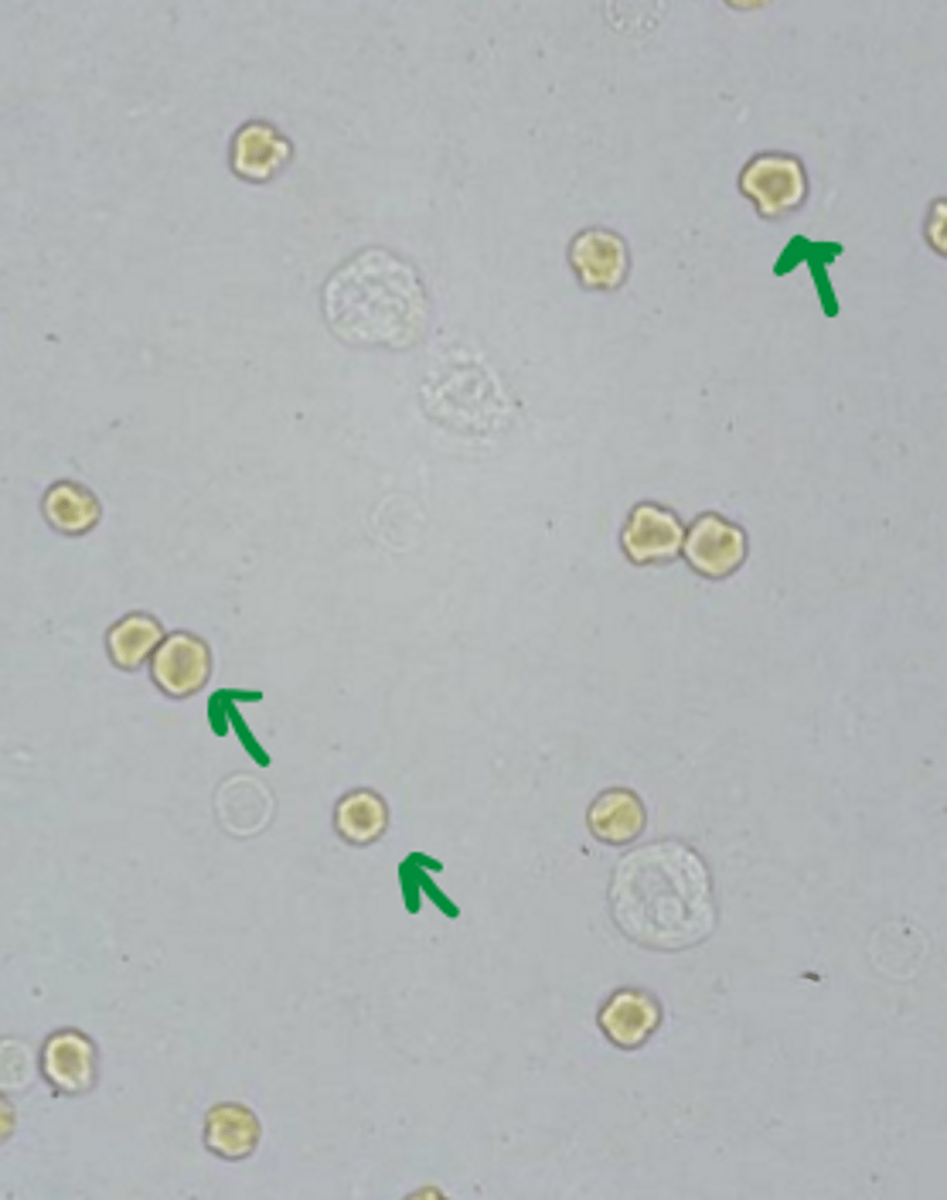

thrombocyte

exotic

lymphocyte

exotic

round, dark staining nucleus

small amount of cytoplasm